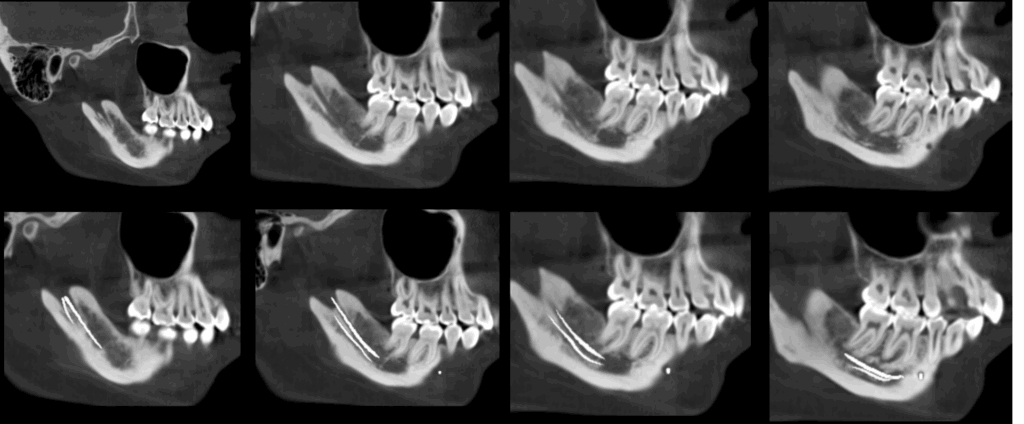

A la evaluación de la tomografía de cráneo completo se encontró un hallazgo imagenológico en el cuarto cuadrante, se observó la bifurcación del conducto dentario inferior que iba desde su entrada por el agujero mandibular y se orienta caudal al conducto dentario principal para volver a unirse con el mismo a nivel apical de la primera molar.

CORTES TANGENCIALES